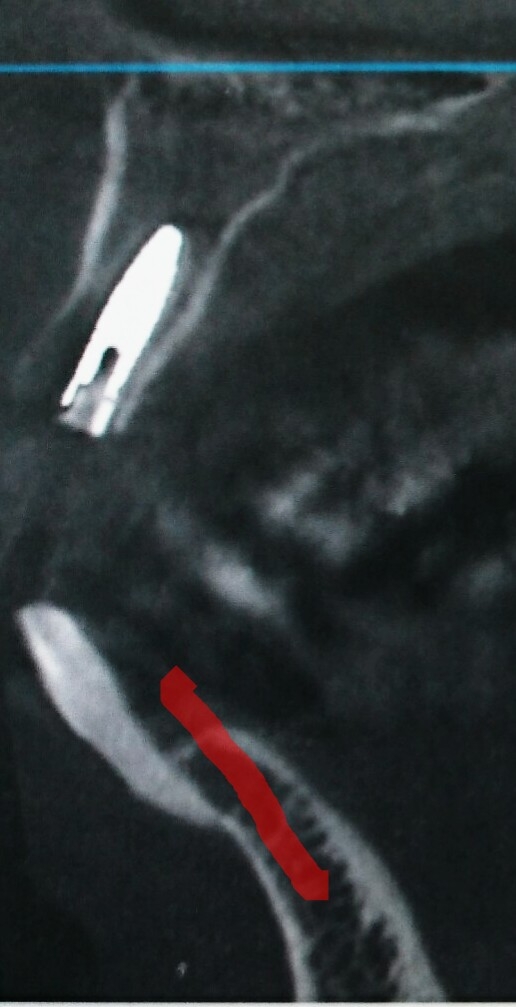

【インプラント立案から埋入までの時系列のレントゲン(2Dや3D)を提示します。是非ご覧下さい❗】レントゲン前歯根っこにヒビが入り冠脱離!レントゲンインプラント・プラン❗レントゲン3D・シミュレーション❗インプラント抜歯即時埋入インプラント❗(本日術後のCTです!上の白い棒状が埋入したインプラントです!因みに下の天然歯をご覧下さい。骨にわずかについているって感じですよね!赤いラインを引いた所に歯が植わっていればしっかりしている感じですが、繰り返しになりますが、天然歯は骨にわすがにくっついているって感じですよね!ですからきちんとケアをしないと歯周病で歯が抜けることもしばしばあるんです。一般の歯周病健診にも是非いらしてください!特に歯を磨いていて歯茎から血が出るかたは歯茎が潰瘍(かいよう)になっています!処置が遅いと胃潰瘍と同様大変なことになりますから。歯周病健診は保険適応です!是非いらしてください!なんと1本の歯の価値は約40万円です!大切になさって下さい!